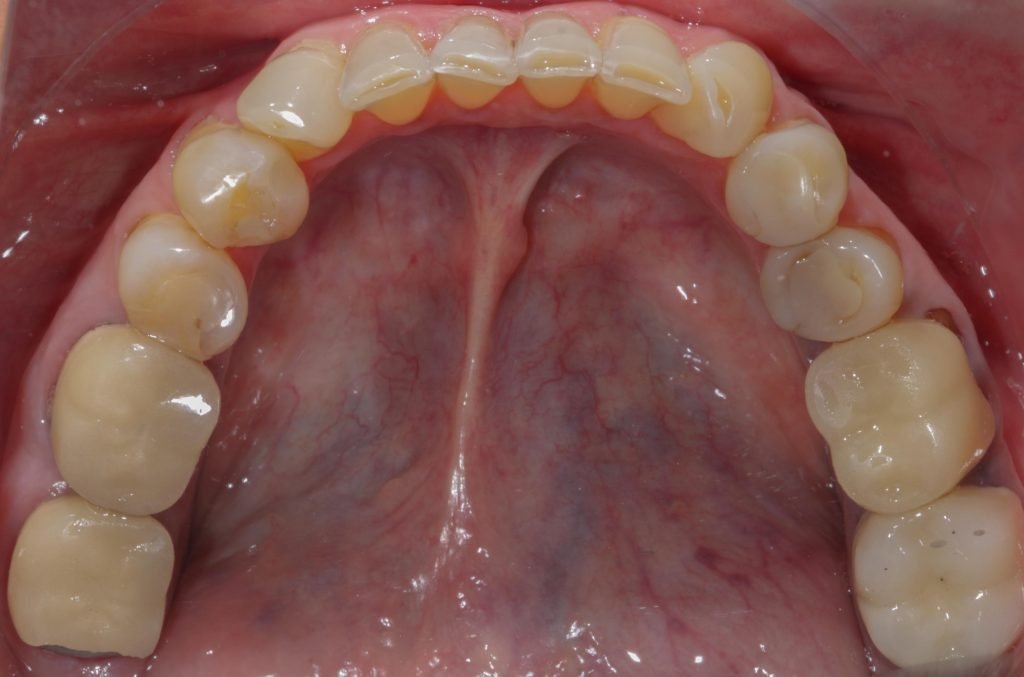

Punto Bajío Casos Clínicos Prótesis Fija sobre Implante unitario Inicio Provisional Final Prótesis Parcial Fija sobre 2 Implantes 2 Implantes Final Prótesis Bucal Removible Inicial Inicial Superior Inicial Inferior Rayos X Inicial Rayos X Inicial Frontal Final Final Superior Final Inferior Prótesis Parcial Fija/ Coronas de Circonio Sonrisa Inicial Foto Inicial Foto Inicial Inferior Foto Final Inferior Foto Final Sonrisa Final Prótesis Total Protesis Inmediatas 1 Protesis Inmediatas 2 Prótesis Removible/ Coronas Metal-Ceramica Carillas Incrustaciones Endodoncia